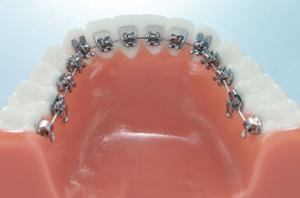

• L’orthodontie linguale

L’orthodontie linguale est une technique véritablement invisible puisque les attaches sont collées sur la face interne des dents.

Elle est cependant plus coûteuse et moins confortable pour le patient (irritation linguale, trouble de la phonation par zozotement, accès plus difficile au brossage).

Une solution permet de concilier la diminution de l’inconfort et la discrétion : une technique « mixte » avec des attaches collées sur la face interne au niveau des dents du haut et sur la face externe pour les dents du bas (moins visibles lors du sourire).